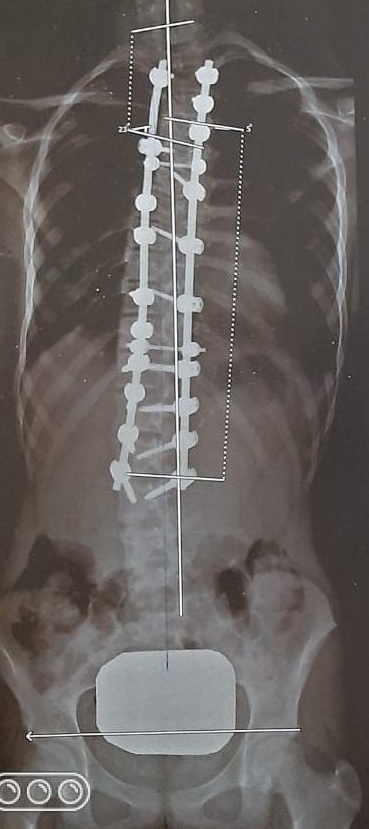

Cirugía de deformidad: Tratamiento de escoliosis idiopáticas o congénitas, para evitar el empeoramiento de la curva de la columna y devolver la estabilidad y estética de los pacientes. Dichas cirugías se realizan por técnica convencional debido a que necesitan correcciones amplias.